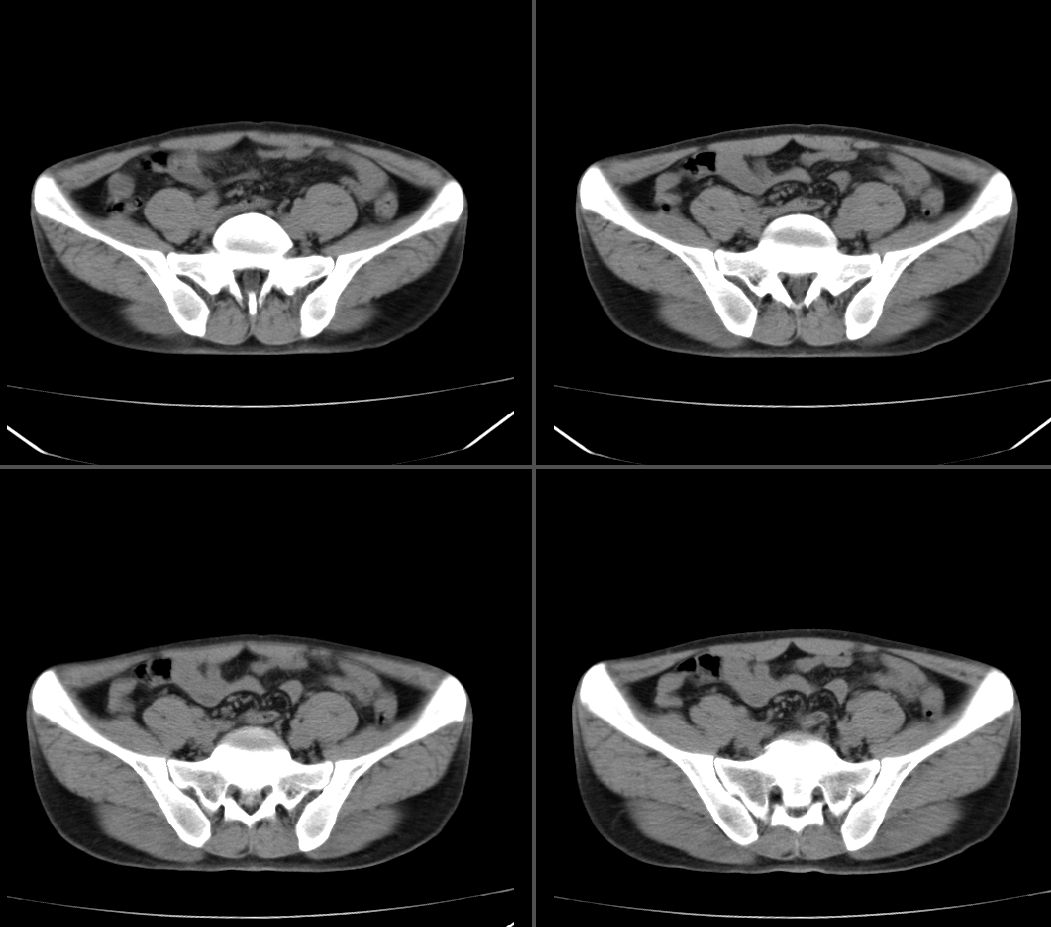

标题: CT23964:45岁,男性,发现右下腹包块半年,余病史不详,请 [打印本页]

标题: CT23964:45岁,男性,发现右下腹包块半年,余病史不详,请

定位:右腹直肌鞘下部

病灶特点:分界清,边缘光整,囊性密度,病灶成长椭圆形,病灶处腹直肌受压萎缩,病灶与膀胱处有相似密度管状灶(该征象因肠道未作准备,不能确切)

右腹直肌腱鞘来源,韧带样纤维瘤可能性大,病变有侵袭性,右侧耻骨联合有骨质缺损。

鉴别:肌纤维瘤样增生,神经源性病变。